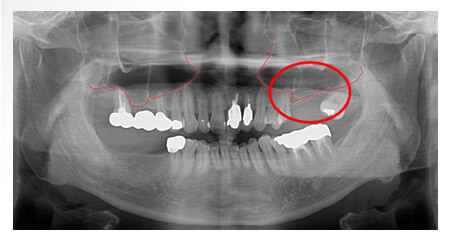

X 光片

術後-標記處補骨並植牙